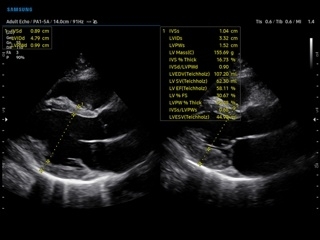

- Кардиология и ангиология — комплексные кардиоваскулярные исследования;

- Кардиологический пакет расчетов, режим CW;

- M — одномерный режим для исследования сердца, анатомический М-режим (необходим кардиопакет), CM-цветной М-режим (необходим кардиопакет);

- Кардиопакет, включающий тканевый допплер (TDI) + анатомический М-режим + цветной М-режим (CM) + программное обеспечение;

- Пакет кардиологических исследований: М-режим: измерение диаметра аорты, передне-заднего размера ЛП, толщины МЖП (систолическая и диастолическая), толщины ЗСЛЖ (систолическая и диастолическая), размеров ЛЖ и ПЖ (систолический и диастолический), ФВ (Teichholz). B-режим: измерение диаметра аорты (восходящей, дуги, нисходящей, на уровне синусов Вальсальвы, на уровне створок аортального клапана), определение размеров ЛП и ПП (максимальный, минимальный, систолический, диастолический, переднее-задний, верхнее-нижний, медиально-латеральный), расчет объемов ЛП и ПП, объемов ЛЖ (метод «Площадь-Длина», метод дисков (Simpson)), массы миокарда ЛЖ, индекса массы миокарда ЛЖ. CD-режим (ЦДК): измерение радиуса ПФСМР (PISA), полуколичественная оценка трансмитрального, транстрикуспидального, трансаортального и транспульмонального кровотока (оценка регургитации), оценка аномальных сбросов крови через МПП И МЖП. PW-режим (импульсно-волновой допплер): автоматическая, полуавтоматическая и ручная трассировка допплеровского спектра митрального, аортального и трикуспидального клапанов, клапана легочной артерии, кровотока в выходном тракте ЛЖ и ПЖ (пиковая/средняя скорость, пиковый/средний градиент давления, время изоволюметрического расслабления ЛЖ, время ускорения, замедления, выброса), оценка кровотока легочных и печеночных вен. CW-режим (постоянно-волновой допплер): программы расчета работы митрального, аортального и трикуспидального клапанов, клапана легочной артерии;